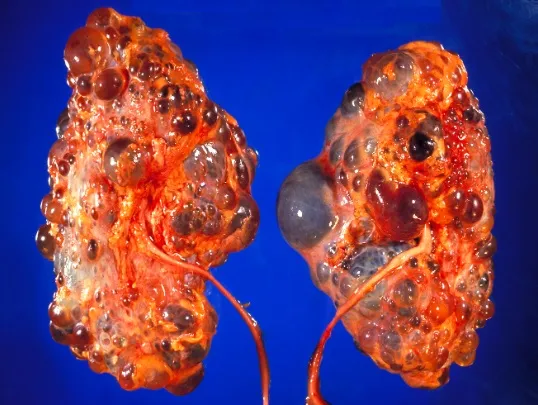

Injúria Renal Aguda (revisão Lancet 2025)

Injúria Renal Aguda (revisão Lancet 2025)